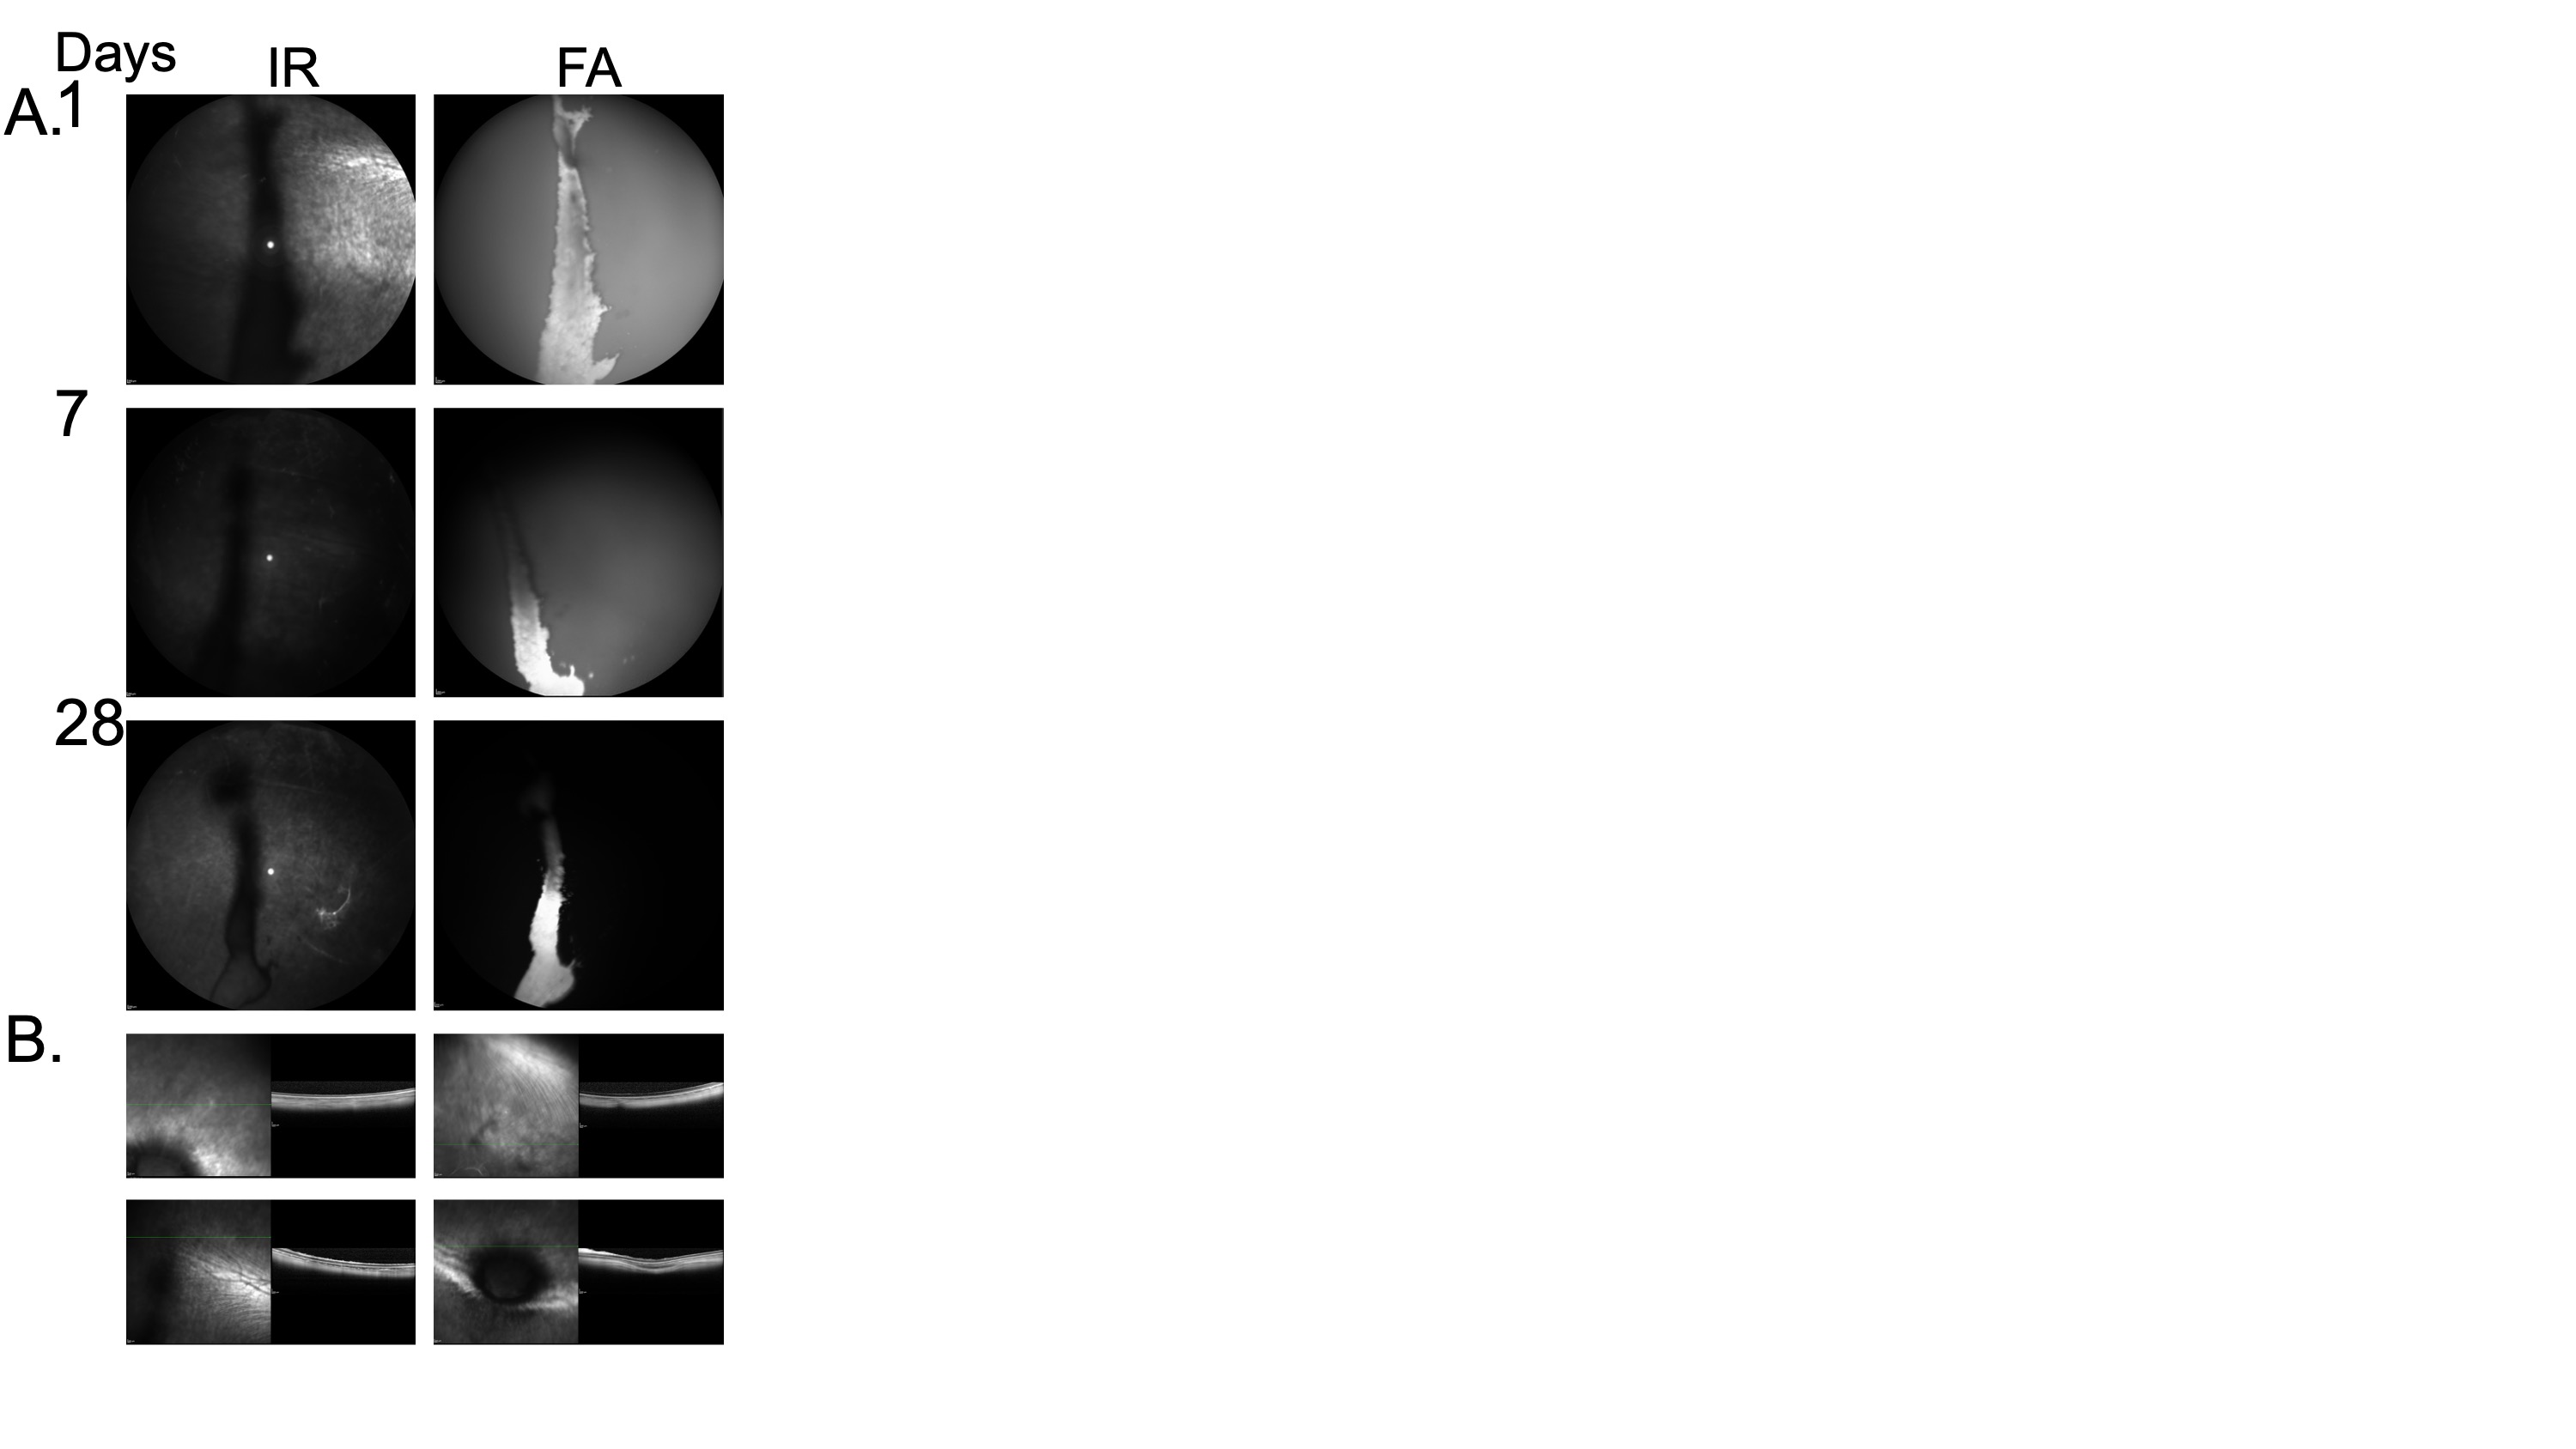

Figure 2. Cry-V96 demonstrates prolonged intravitreal retention over 28 days following a single intravitreal injection, while maintaining retinal integrity. A) Spectralis OCT was used to monitor the pharmacokinetics of a single intravitreal injection of ~ 300 μM fluorescein-labeled cry-V96 in NZP rabbits. Infrared reflectance (IR) and fluorescein angiography (FA) imaging revealed a visible depot throughout the 28-day period. Diffusion from the depot (indicated by whitish background signal) was clearly observed on days 1 and 7. B) Retinal sections obtained on day 28 at different spots, prior to euthanasia, showed preserved retinal structure, confirming the absence of observable toxicity.